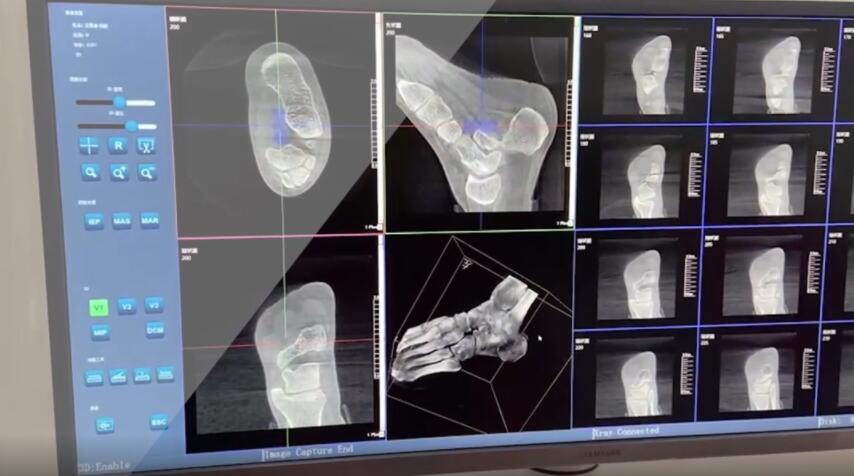

在術前,我們需要做三維掃描的CT檢查,我們必須要有CT的片子,還要有三維的重建。

在術中,我們怎么去判斷關節(jié)面平不平整呢?常規(guī)的正側(cè)位影像是不能判斷的。有些醫(yī)生為了準確的判斷,可能會選擇做開放性的手術,把關節(jié)暴露出來,在眼睛的直視下判斷關節(jié)面平不平整。但是關節(jié)全部打開,無疑增加了病人的創(chuàng)傷,而且增加了患者的恢復時間。所以如果在術中我們有三維影像的支持,對醫(yī)生做手術而言就會事半功倍,而且能夠大大的增加手術準確度,增加患者術后的預后。所以在術中有三維影像的支持是非常必要的!

三維影像 看透關節(jié)內(nèi)骨折的“眼睛”